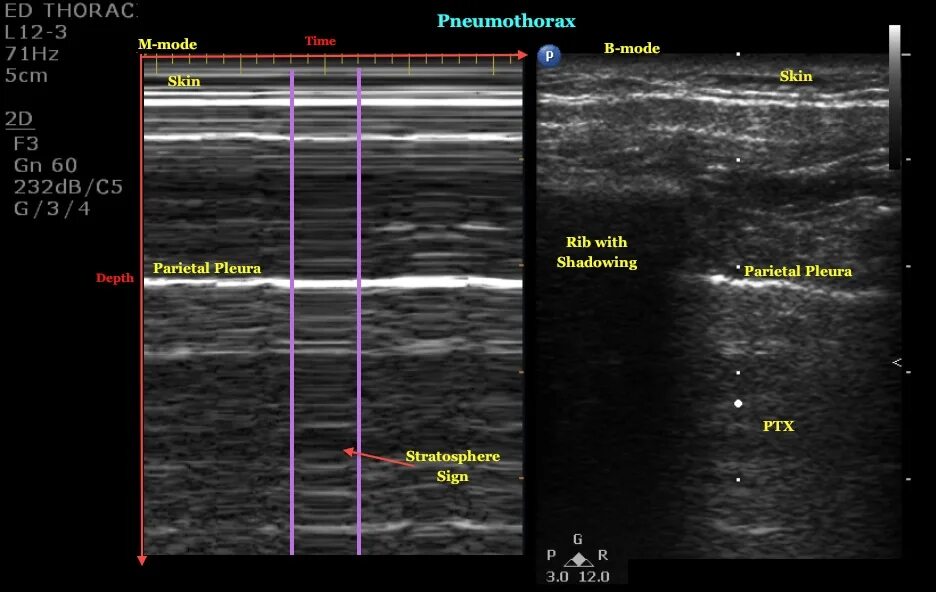

M mode